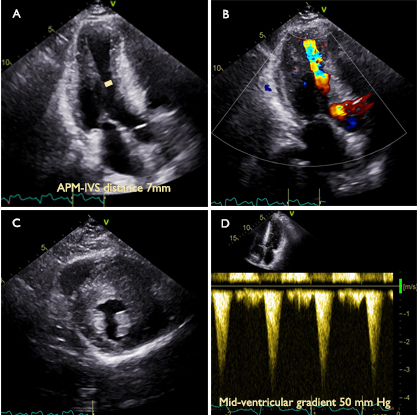

Methods: MVO was defined as a mid-ventricular gradient of ≥ 30 mmHg at rest or after being provoked. Patients with both left ventricular outflow tract obstruction and MVO were included in the MVO group. APM-IVS distance was analyzed on apical three chamber view at end-diastole (Image 1).

Results: A total of 2125 patients with HCM were recruited from both the outpatient and inpatient settings of the Department of Cardiovascular Surgery at Fuwai Hospital. Among these, data from 1453 patients with measurable APM-IVS distances were analyzed. Of the 1453 patients, 596 had MVO, while 857 did not exhibit MVO. Multivariate logistic regression analyses showed that APM-IVS distance was an independent indicator of MVO (adjusted odds ratio [95% confidence interval (CI)]: 0.487 [0.448–0.529]). The APM-IVS distance demonstrated the highest diagnostic accuracy in identifying MVO, exhibiting an area under the receiver operating characteristic curve of 0.949 (95% CI: 0.937–0.960). An APM-IVS distance greater than 12 mm was associated with the absence of MVO, demonstrating a negative predictive value of 95.7%. Conversely, an APM-IVS distance of 8 mm or less was indicative of the presence of MVO, with a positive predictive value of 92.8% (Image 2). The presence of a smaller APM-IVS distance was correlated with increased incidence of left ventricular apical aneurysm and MVO, elevated levels of N-terminal pro brain natriuretic peptide, as well as higher New York Heart Association functional class. Among those with MVO, 198 patients underwent surgical myectomy and were followed up after a median time of 12 months. APM-IVS distance increased from 7.6±2.2 mm to 18.9±4.9 mm, and the peak mid-ventricular gradient decreased from 50 mm Hg (36–57 mmHg) to 3 mmHg (3–7 mmHg) at follow-up.